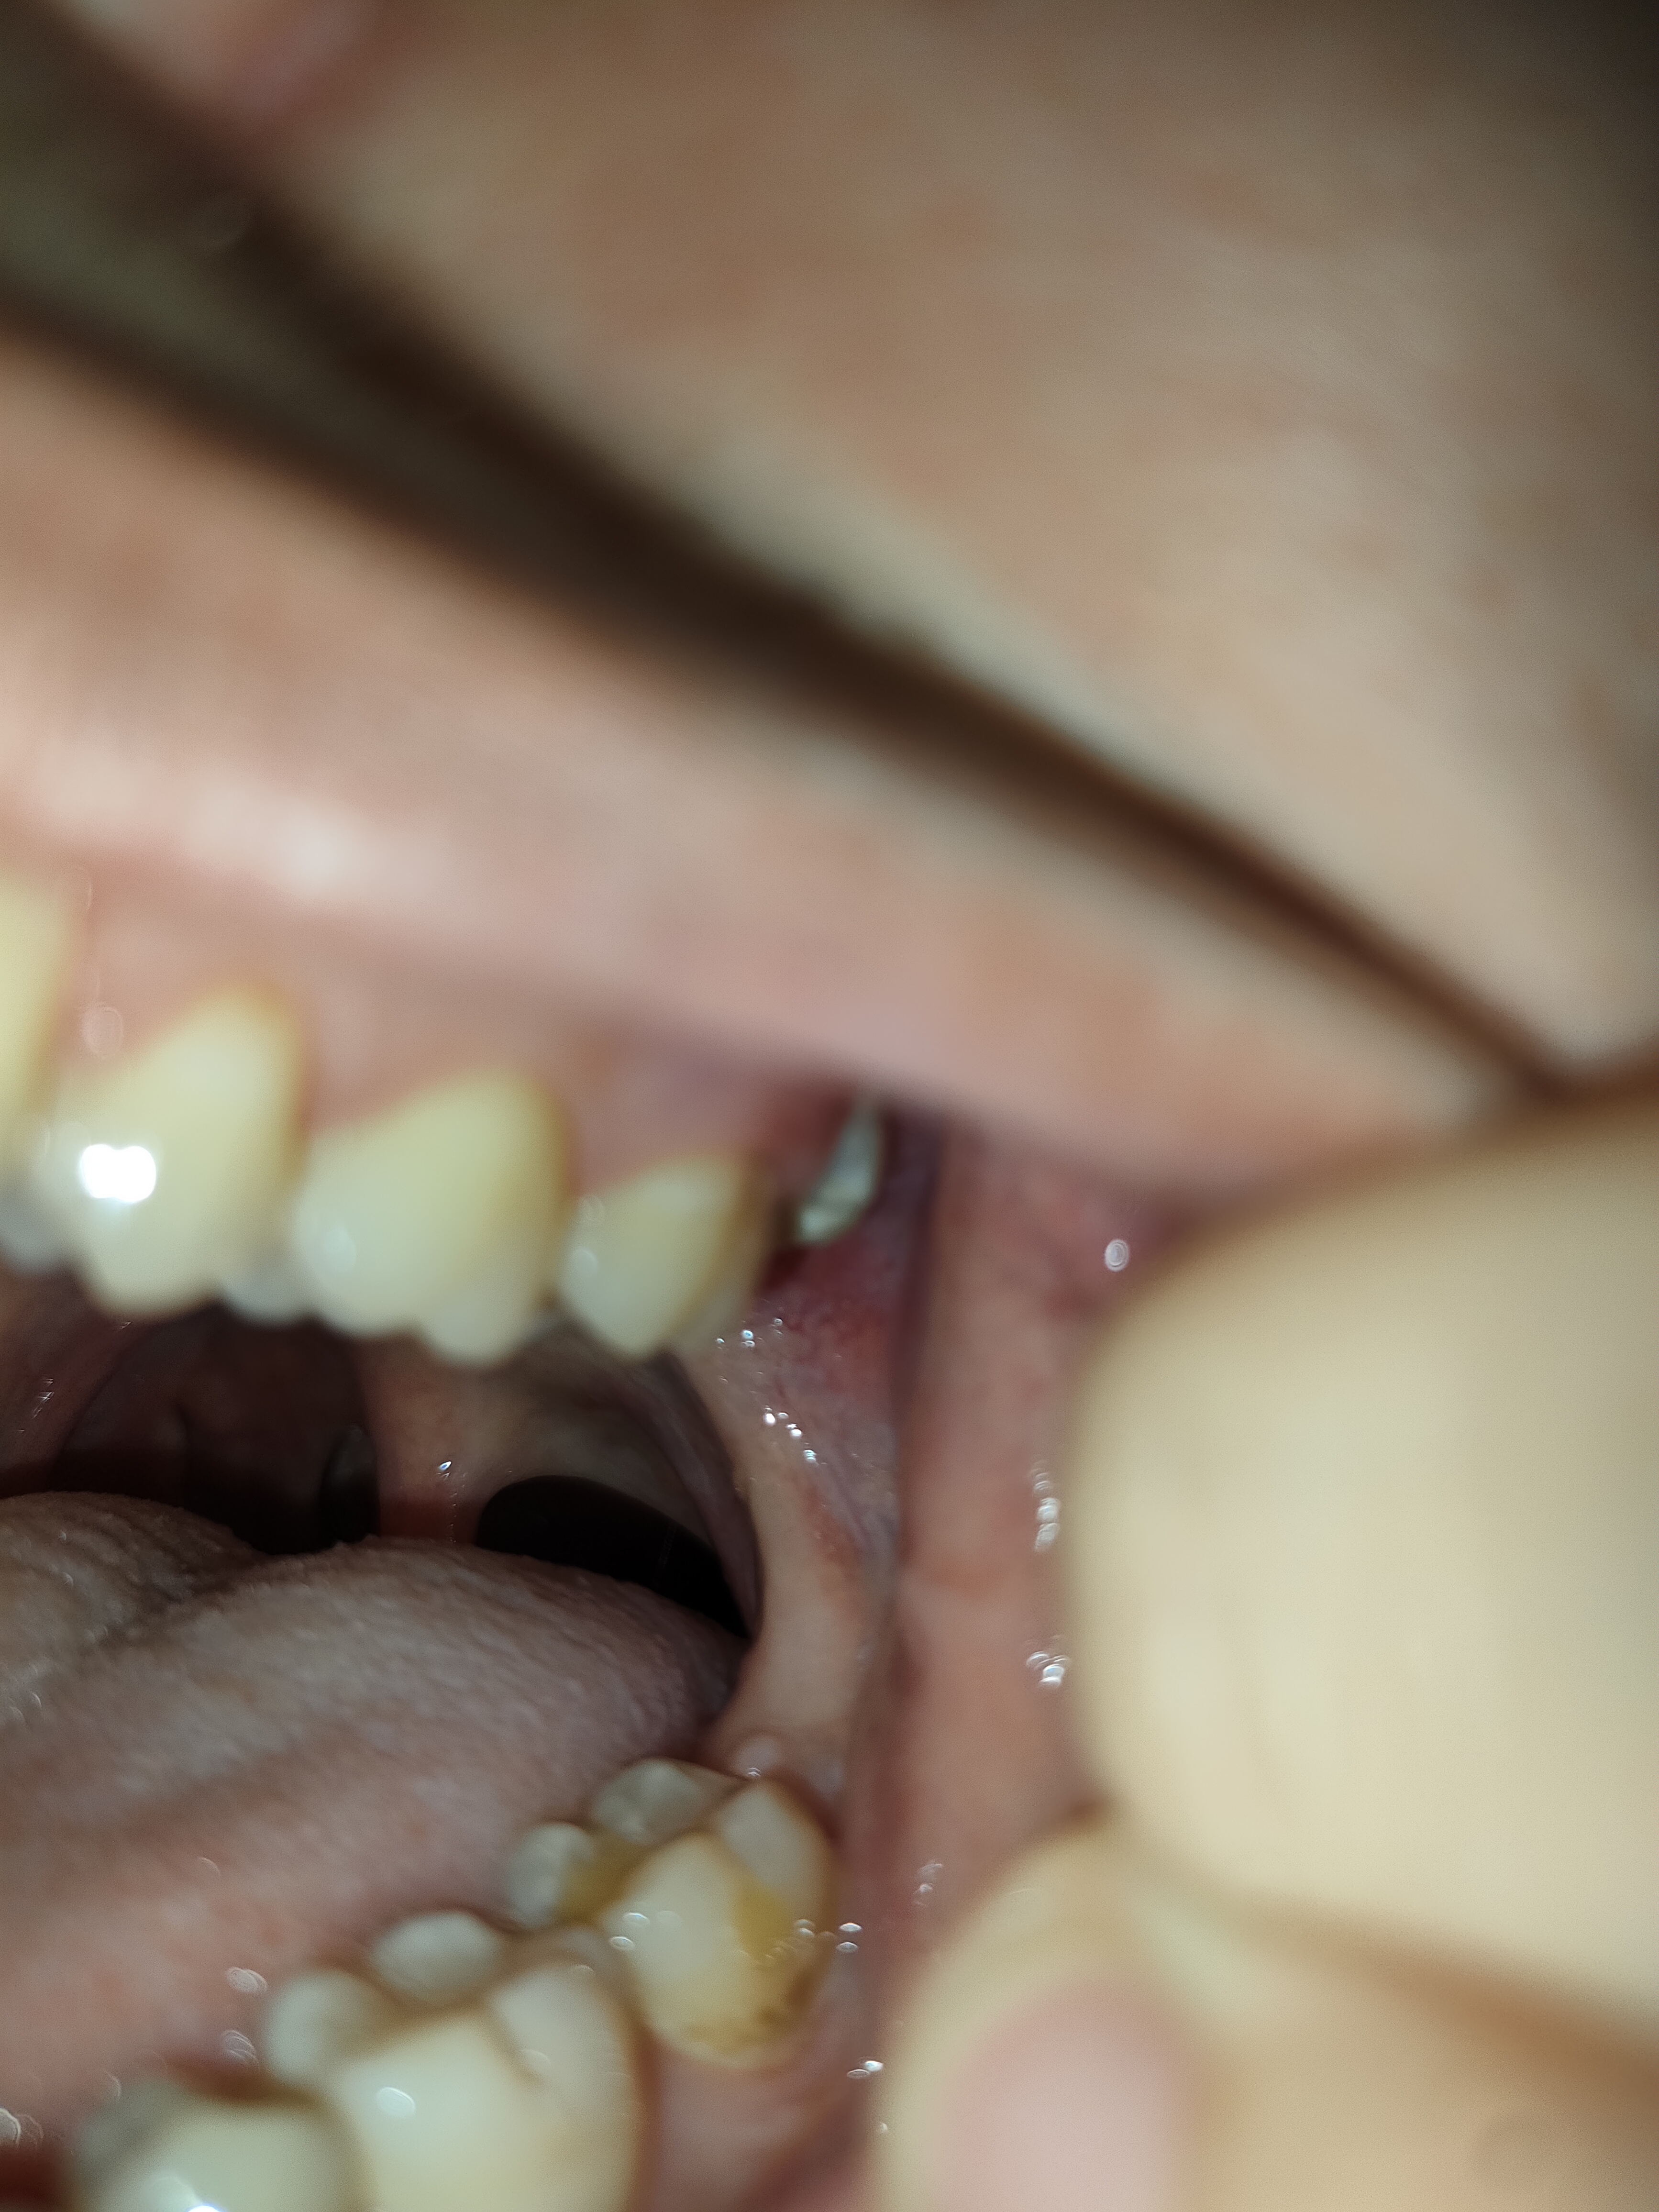

1000070960.jpg 313Кб, 1117x832

1117x832

1000070961.jpg 180Кб, 882x704

882x704

Зуб пятерка. Возможно такое вылечить, анонче? Отклолся как то, вообще не болит.